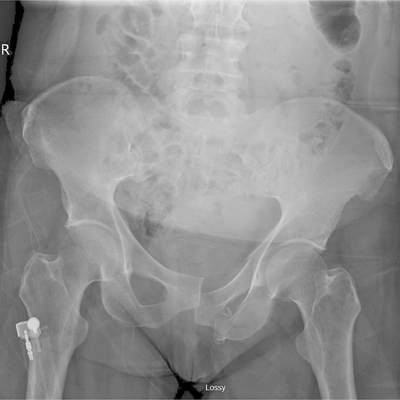

Click on an image below to view more info.